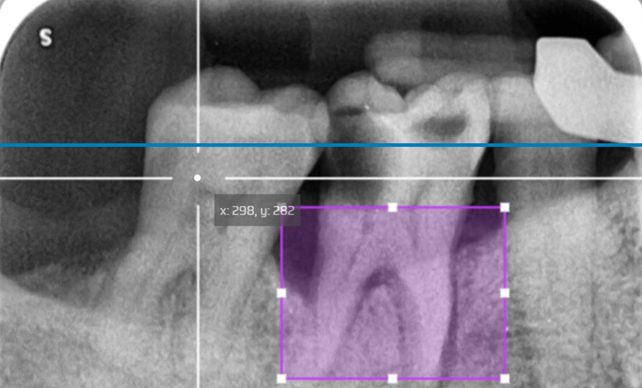

Can the dental sector benefit from AI? How can a Hybrid Classification Model improve Reliability, not just Accuracy?

A Hybrid AI model that combines the full X-Ray scope with a critical, detailed area…